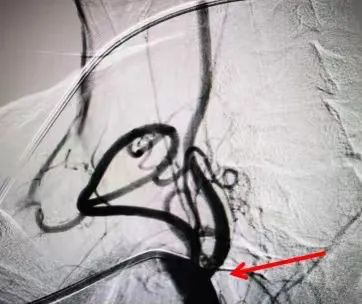

患者,男,65岁,因“头晕、饮水呛咳”入院,核磁检查提示右侧延髓、小脑半球梗死,头颈部CTA检查提示右椎动脉开口重度狭窄,考虑为本次脑梗死责任血管,为进一步防范更严重脑卒中发生,于住院1周后经桡动脉途径顺利行右椎动脉支架植入术。术后患者病情稳定,头晕好转,饮水稍呛咳,吞咽水试验2级,四肢活动正常,住院12天后顺利出院。

椎动脉支架植入后造影图像